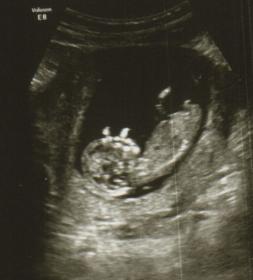

Looks like a baby boy :-)

mayb boy :)

Boy

Maybe a girl?? It seems like an odd capture of the nub, though, so who knows!

not sure it may be part of foot or nub